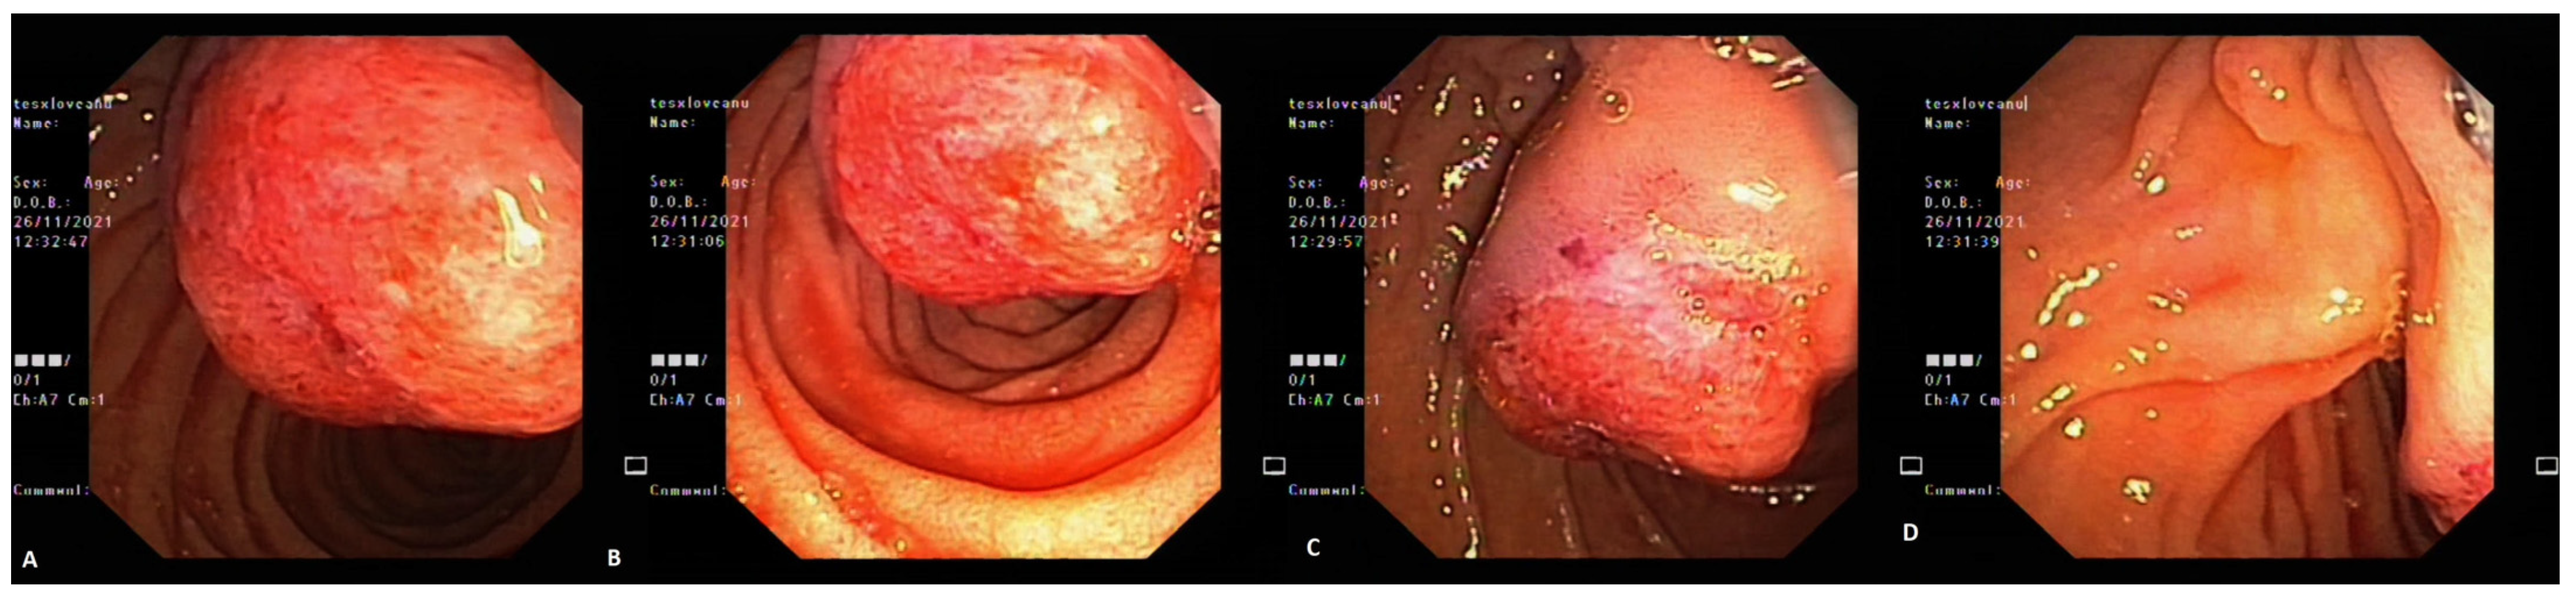

3. Case Report 2